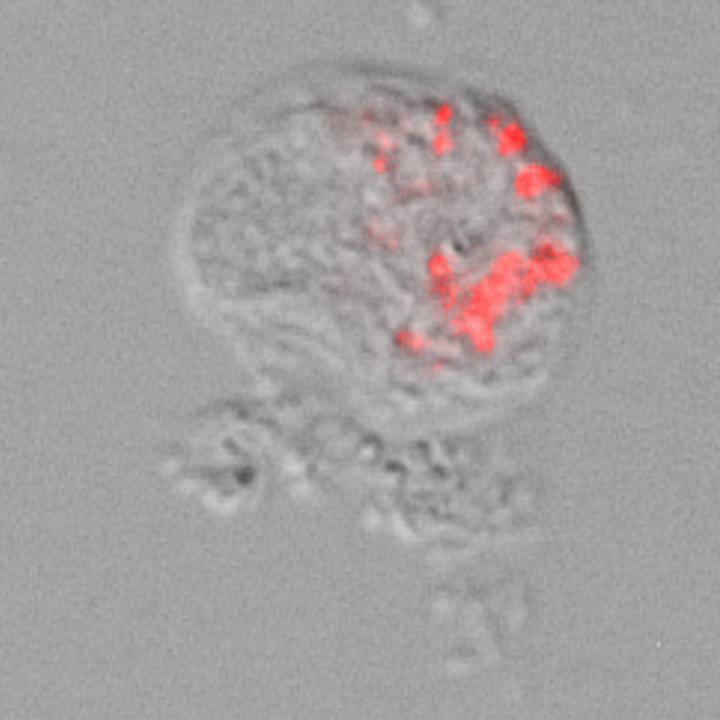

image: Light microscope image and illustration of a Thecofilosea amoeba with intracellular Legionellales bacteria ('Ca. Pokemonas kadabra'). The bacteria were stained red by so-called 'fluorescence in situ hybridization'.

Bacteria of the order Legionellales have long been of scientific interest because some of these bacteria are known to cause lung disease in humans and animals - such as 'Legionnaires' disease', which is caused by the species Legionella pneumophila and can sometimes be fatal. Legionellales bacteria live and multiply as intracellular parasites in the cells of organisms as hosts. In particular, the hosts of Legionellales are amoebae. The term 'amoeba' is used to describe a variety of microorganisms that are not closely related, but share a variable shape and crawling locomotion by means of pseudopods. 'We wanted to screen amoebae for Legionellales and chose a group of amoebae for our research that had no close relationship to the hosts that were previously studied. The choice fell on the amoeba group Thecofilosea, which is often overlooked by researchers,' explains Marcel Dominik Solbach.

And indeed, the spherical Thecofilosea serve as host organisms for Legionellales. In Thecofilosea amoebae from environmental samples, the scientists were able to detect various Legionellales species, including two previously undescribed genera and one undescribed species from the genus Legionella. 'The results show that the range of known host organisms of these bacteria is considerably wider than previously thought. In addition, these findings suggest that many more amoebae may serve as hosts for Legionellales - and thus potentially as vectors of disease. To investigate this further, we are now sequencing the complete genome of these bacteria,' said Dr Kenneth Dumack, who led the project.